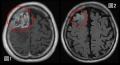

図1は膠芽腫の典型的な画像所見です。一般的にこのような画像所見を認めれば速やかな治療介入が行われるため、膠芽腫の自然歴を追うことは難しいとされています。しかし、こういった症例においても、過去に何かしら別の理由、例えば脳ドックや頭部外傷、別の脳疾患のフォロー目的などで頭部の画像検査をされていることがあるということに気づきました。その中には過去画像で何も病変がないものもあれば、膠芽腫の芽とも考えられるような微小な病変を認めるものもあり、こういった画像こそが膠芽腫の画像上の起源を推定できるデータになるのではないかと考えました。図2は図1と同一患者の画像ですが、7.5ヶ月前のものであり、微小ではありますが後方視的に見れば異常所見を認めています。